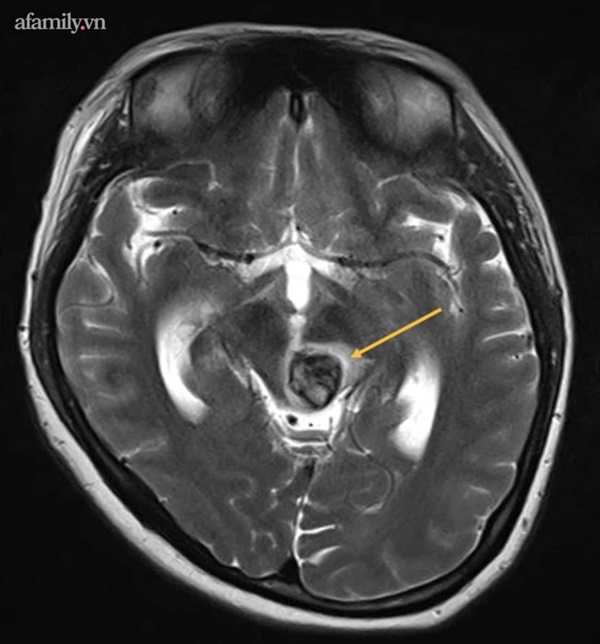

Hình ảnh dị dạng mạch máu não của sản phụ.

Phần thân não của sản phụ bị tổn hại, xuất huyết nặng dẫn đến hôn mê, ảnh hưởng lớn đến hệ hô hấp và tuần hoàn. Trường hợp này có nguy cơ tử vong cao nếu không được cấp cứu và điều trị kịp thời.